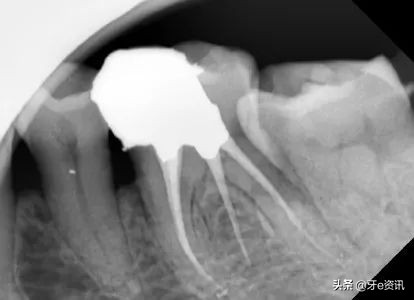

二、医方在对患者治疗过程中,发生扩大针折断于根管内长约2mm,此为根管治疗过程中难以完全避免的情况。

当医生发现在治疗中有器械折断时,会立即让您拍一张x片以确定断针的部位,断针的长度及其与周围组织的解剖关系。

如果断针发生的部位较浅,大多可以取出,并不影响下一步的治疗和患牙的预后。

有的时候如果针断的部位过深或折断在根管弯曲处时,并不是所有的断针都能取出,有时由于断针发生在根管过于弯曲的部位或断针嵌塞过于紧密从而未能取出,此时您也不要害怕,因为器械折断绝大多数都发生在根管中,不会超出牙根,更不可能进入血液(牙根被致密的骨组织包绕,而不是血管组织)流到您身体的其他部位,因而有患者担心断针会引起身体其他部位的疾病是不必要的。